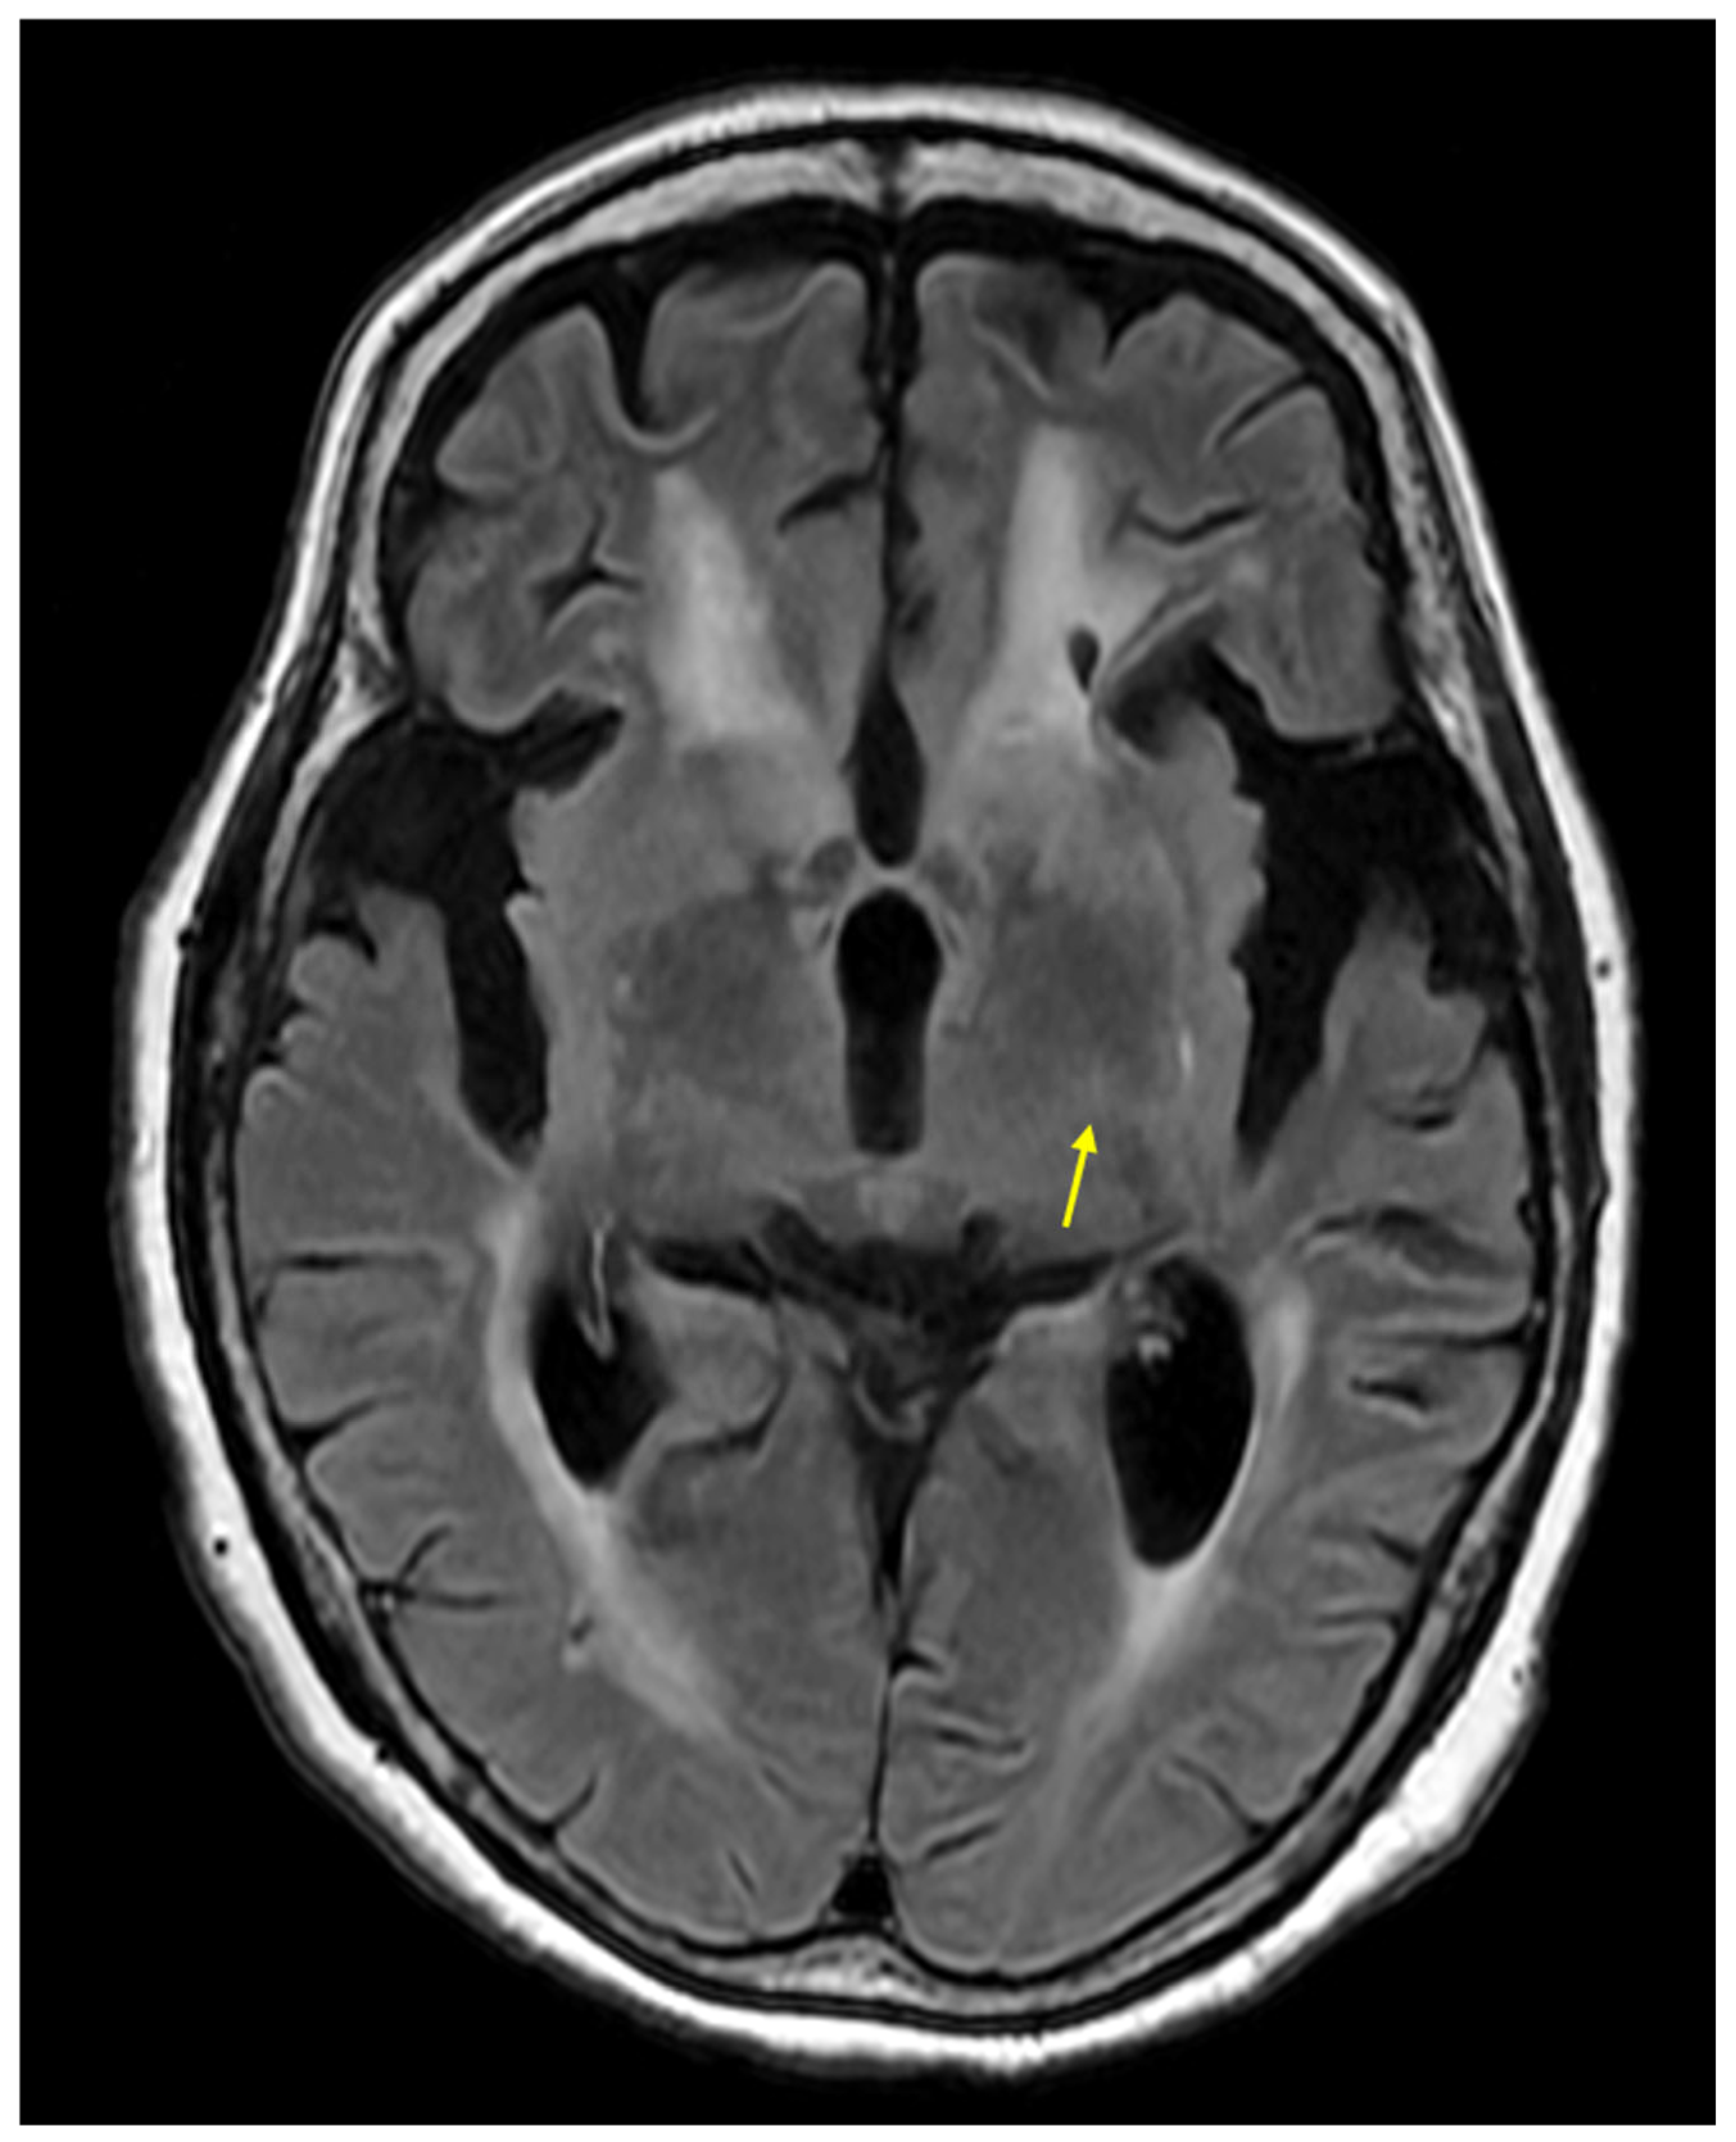

- Protogerou, G.; Ralli, S.; Tsougos, I.; Patramani, I.; Hadjigeorgiou, G.; Fezoulidis, I.; Kapsalaki, E.Z. T2 FLAIR increased signal intensity at the posterior limb of the internal capsule: Clinical significance in ALS patients. Neuroradiol. J. 2011, 24, 226–234. [Google Scholar] [CrossRef] [PubMed]